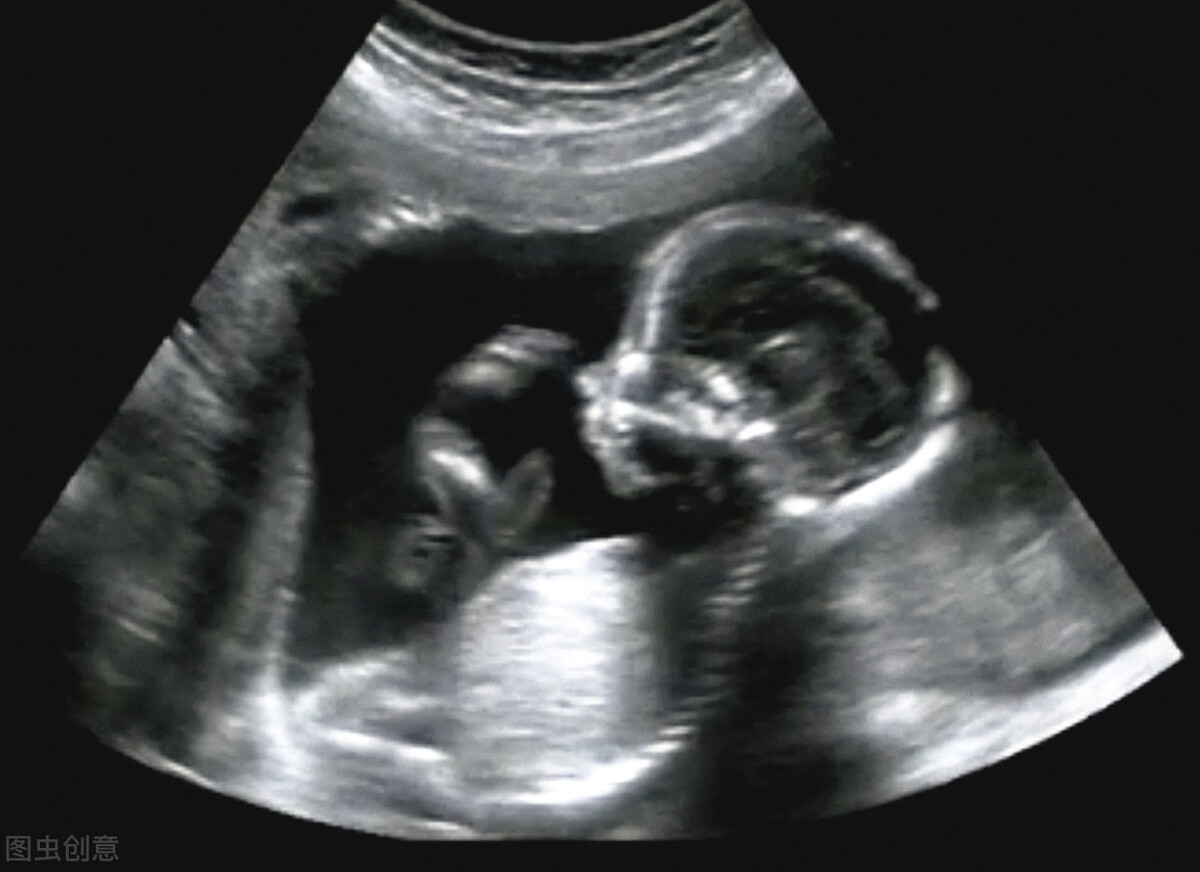

做四维大排畸时

四维大排畸一般在孕23周至26周做,主要是看孩子的脊柱、大外观等等有没有明显的缺陷。

这个时候如果确认没有什么大问题,宝爸宝妈就可以比较放心了。

四维的图片会给出孩子脸部的特写,大致都可以看出孩子长得像爸爸还是妈妈了。

可以说,这是我们和孩子的第一次“正式见面”。

如果在此之前我们对孩子还是“一无所知”的话,那么做四维就是让我们和孩子第一次建立起了比较明确的链接。

我家大宝做四维时睁开了眼睛,很多朋友说这不可能,在羊水里怎么可能睁开眼睛,可报告图片上确实是睁着眼睛的。

由此我对老公说,这孩子将来可能会比较敏感和早熟,很可能是超声波的噪音打扰了他,所以他睁了一下眼睛,正好这一瞬间被保存了下来。

果不其然,大宝确实是个对外界的评价很敏感的孩子,并且比同龄的男孩子显得早熟。

所以说,宝爸们要珍惜这第一次和孩子“见面”的机会,说不定会一下子唤起内心父爱的火苗。

有些私立医院做四维的时候宝爸可以陪同检查,检查的地方还会有一个放大的显示屏,可以让宝爸宝妈更能看清孩子的样子,还可以看到孩子在肚子里的各种动作。有些医院还会把四维彩超做成光盘,留给爸爸妈妈做纪念。

这些经历对于将来在育儿路上要携手走多很多春秋的宝爸宝妈来说,都是很珍贵的记忆。